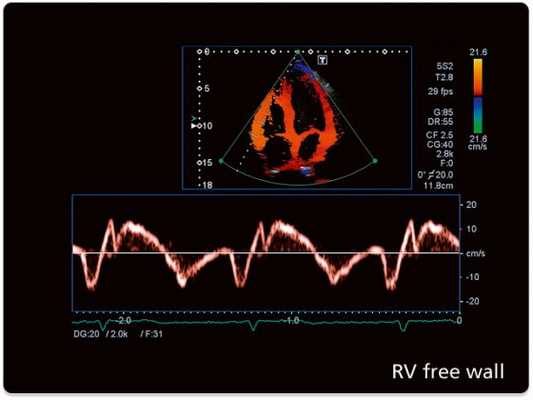

Эхокардиография и цветное допплеровское картирование

![Эхокардиография после протезирования клапанов]()

Допплер-эхокардиография позволяет выявить скорость потока через протез клапана, что позволяет определять градиенты давления с использованием модифицированного уравнения Бернулли (градиент давления = 4 х скорость в квадрате). Отличная корреляция была установлена между допплеровским методом и инвазивным измерением давления двойным катетером, выполненным одновременно на различных протезированных клапанах. Однако, несколько моделей инвитро показали завышение градиента на аортальном протезе, которые определяются по допплеровским скоростям по сравнению с катетер-производными градиентами. Расхождение данных меньше в протезе с большим опорным кольцом. Потенциальные источники в разнице между допплер-производными и катетер-производными перепадами давления на протезах должны быть учтены, но это не является большой проблемой в выявлении дисфункции протеза.

Непрерывно-волновая допплерография может быть использована для оценки функциональной площади отверстия протеза аортального и митрального клапанов. Время полуспада давления (РНТ) метод, используемый для определения стеноза нативного митрального клапана, обычно переоценивает площадь митрального протеза. Протез клапана изначально стенотический в разной степени по сравнению с соответствующим родным клапаном, поэтому скорость потока через нормальный протез клапана выше, чем ожидаемый на родном клапане. Нормальная скорость протезного потока (следовательно, максимальный и средний градиенты давления) зависит от типа и размера протеза, его расположения и сердечного выброса. Следовательно, очень важно знать нормальные диапазоны скоростей потока для определенных типов протезов для сравнения с измеренными значениями. Поскольку гемодинамика протеза зависит от различных факторов, рекомендуется выполнить базовое допплеровское эхокардиографическое исследование в раннем послеоперационном периоде (сделать «отпечаток» функции протеза), так что он может быть использован в качестве эталона для сравнения с последующими исследованиями. Обе ситуации как регургитация, так и обструкция может привести к увеличению скорости потока через протез. Увеличение скорости потока указывает на то, что имеется несоответствующее меньшее отверстие, когда в протезе есть препятствие и при этом нет клинически значимой регургитации или увеличивается объем потока через протез (есть значимая регургитация).

Другие полезные характеристики допплеровского исследования на эхокардиографии протезов позволяет отличить непроходимость от регургитации. Когда на протезе имеется препятствие, кроме увеличения скорости потока пролонгируется длительность период полуспада РНТ (для протезов митрального и трикуспидального клапана). Увеличение скорости потока через обструкцию аортального протеза не сопровождается увеличением скорости в выходном тракте левого желудочка (ВТЛЖ), но увеличивается при тяжелой регургитации. Когда скорость через митральный или трехстворчатый протез в диастолу увеличивается из-за сильной регургитации, РНТ является нормальным или укороченным, а в ВТЛЖ скорость уменьшается, потому что прямоток из-за регургитации в систолу через протез уменьшается (часть крови попадает обратно в предсердие). Состояние высокого сердечного выброса увеличивает скорость на протезе, и это может быть подтверждено путем записи увеличение скорости потока во всех кардиальных отверстиях (ВТЛЖ, атриовентрикулярных клапанах, выходном тракте правого желудочка).